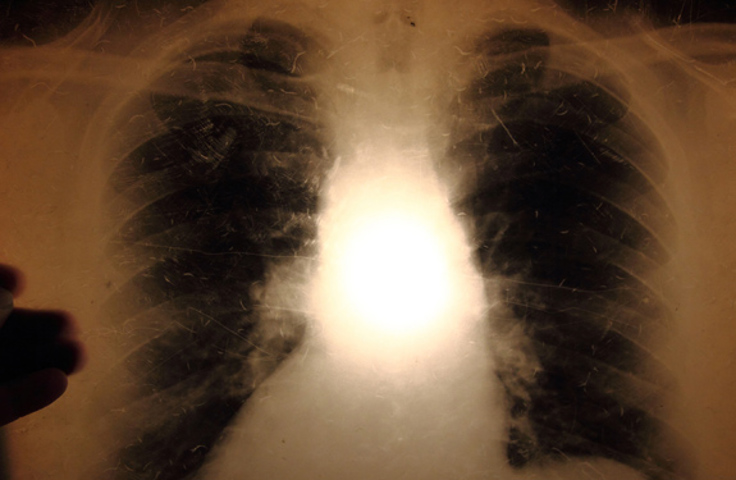

Chest X-rays for tuberculosis (TB) during pregnancy

Chest X-ray examinations for pregnant women are safe with regards to potential harm to the foetus from radiation. The Norwegian Institute of Public Health recommends that chest X-rays are performed on pregnant women as part of the tuberculosis screening to see whether they have pulmonary tuberculosis. If the pregnant woman prefers not to do this, and there is no suspicion of pulmonary tuberculosis, IGRA is an alternative.

X-ray examinations of the lungs of pregnant women are safe with regards to the potential risk of foetal harm from radiation. The International Commission on Radiological Protection (ICRP) estimates that the threshold dose for radiation-induced foetal damage begins at approximately 100 mGy [2,3]. A typical dose to the foetus / embryo during a chest X-ray is less than 0.01 mGy, which is less than 0.01 % (or 1/10 000 part) of the threshold dose for radiation-induced injury. The Norwegian Radiation Protection Authority considers that chest X-rays of pregnant women are safe as long as the examination is justified [4]. The Norwegian guidelines are in line with guidelines from the USA [5].